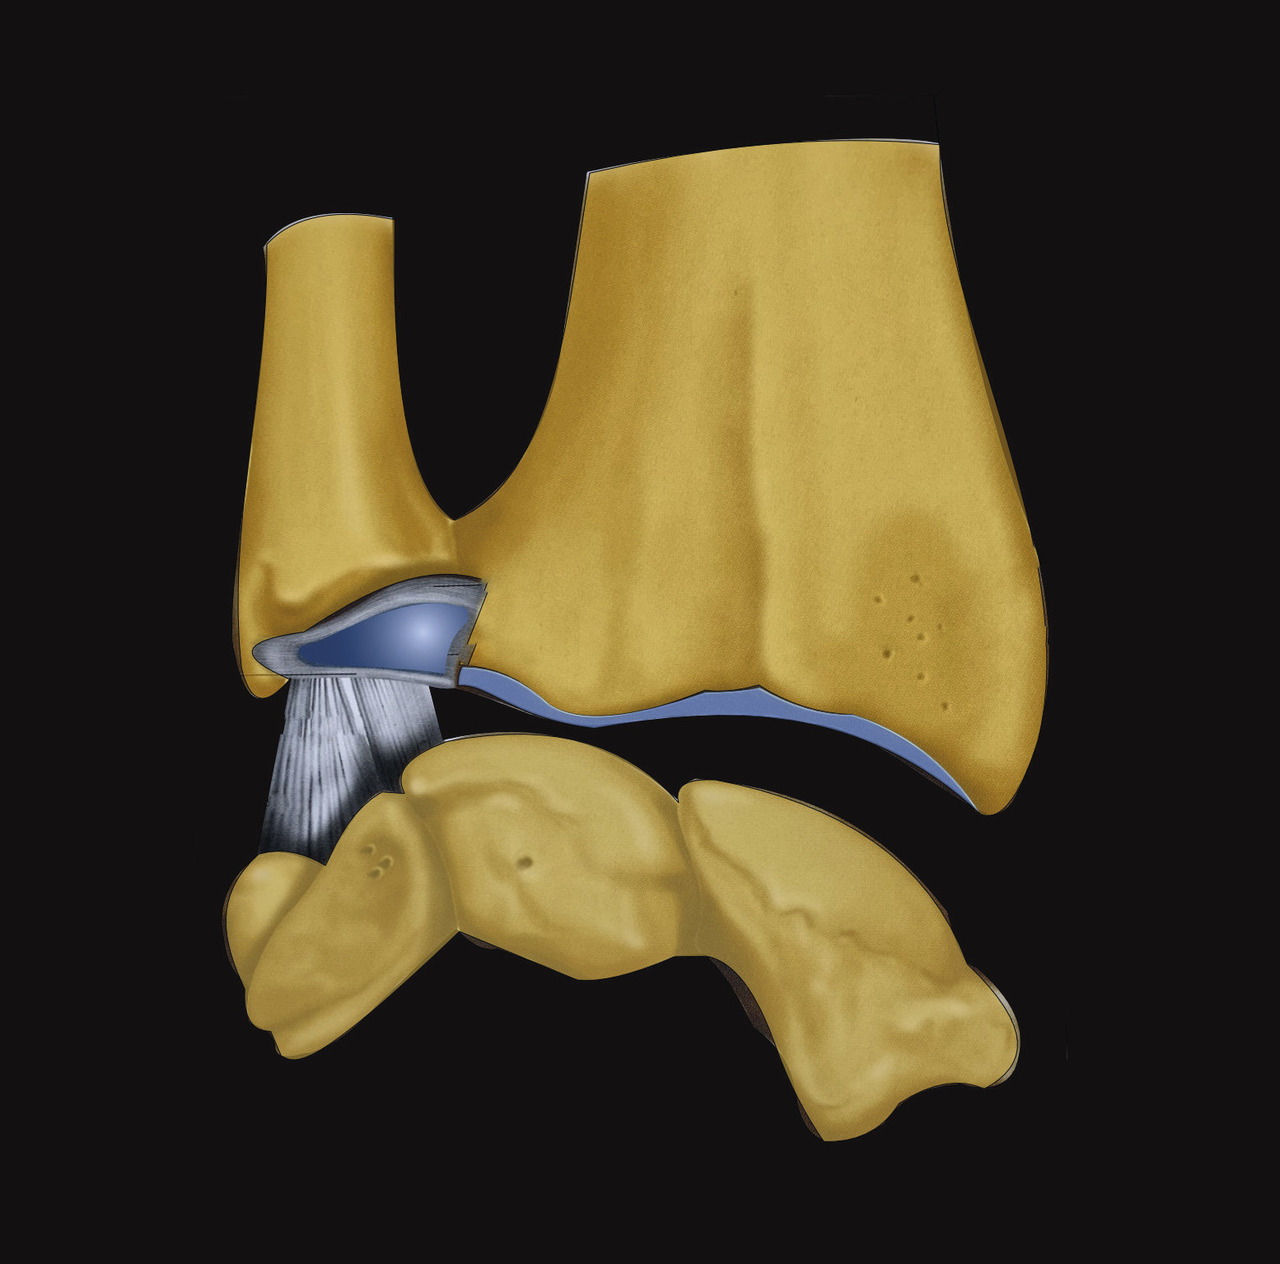

L’extrémité inférieure du radius est biarticulaire, en répondant à la fois au carpe par la glène radiale et à la tête de l’ulna par l’incisure ulnaire du radius, expliquant qu’entre 50 et 80 % des fractures de l’extrémité inférieure du radius ont une participation articulaire.8 Elle constitue un bloc épiphysométaphysaire distal hétérogène et complexe de forme schématiquement triangulaire à base médiale et à sommet latéral qui s’effile par la styloïde radiale (fig. 1).

La surface articulaire distale, encroûtée de cartilage, répond au carpe distalement et présente deux facettes, scaphoïdienne et lunarienne (fig. 3), séparées par une crête de direction antéropostérieure. Cette surface articulaire a une double concavité transversale et sagittale. Il est crucial de retenir qu’elle possède une double inclinaison ventrale (10 à 12° en moyenne dans le plan sagittal) et médiale (22 à 24° en moyenne dans le plan coronal), très spécifique, qu’il faudra s’efforcer de restituer et de maintenir dans le traitement de la composante métaphysaire de ces fractures (fig. 4). L’index radio-ulnaire distal, défini par la longueur relative du radius par rapport à l’ulna, est le troisième critère morphologique à évaluer (fig. 4). Ce dernier, dont les valeurs normales sont très variables, est en moyenne neutre à 0 mm (-3 mm à +2 mm).

Enfin, le complexe ligament triangulaire prolonge la surface articulaire distale du radius sur son versant médial. Il s’agit d’une structure ligamentaire tendue du versant médial et distal de l’extrémité inférieure du radius, sur le pourtour de l’incisure ulnaire jusqu’à la base de l’apophyse styloïde de l’ulna (fig. 5). Ainsi, l’extrémité distale du radius, l’articulation radio-­ulnaire distale, le complexe ligamentaire triangulaire et l’extrémité distale de l’ulna constituent une entité anatomofonctionnelle continue, composite et indissociable. Les lésions associées aux fractures de l’extrémité inférieure du radius, comme les fractures de la styloïde ulnaire ou les lésions ligamentaires du complexe triangulaire, appartiennent donc au même spectre lésionnel. On s’attachera par conséquent à rechercher systématiquement une participation articulaire aux lésions fracturaires et des lésions ligamentaires associées.